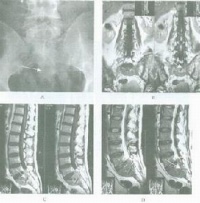

结肿大可压迫邻近器官,表现的压迫症状,例如纵隔淋巴结肿大可致咳嗽、胸闷、气促、肺不张及上腔静脉压迫症等;腹膜后淋巴结肿大可压迫输尿管,引起肾盂积水;硬膜外肿块导致脊髓压迫症等。另有一些HD病人(30%~50%)以原因不明的特许或周期性发热为主要起病症状。这类患者一般年龄稍大,男性较多,病变较为弥散,常已有腹膜后淋巴结累及。发热后部分患者有盗汗、疲乏及消瘦等全身症状。周期性发热(Pel-Ebstein热)约见于1/6患者。部分患者可有局部及全身皮肤搔痒,多为年轻患者,特别是女性。全身搔痒可为HD的唯一全身症状。

HD尚可侵犯各系统或器官:例如肺实质轻浸润、胸腔积液、骨髓引起骨痛、腰椎或胸椎破坏,以及脊髓压迫症等。带状疱疹好发于HD,约占5%~16%。

咽淋巴环病变通常占恶性淋巴瘤的10%~15%,96%为弥漫性原淋巴细胞及组织细胞型淋巴瘤,发生部位最多在软腭、扁桃体,其次为鼻腔及鼻窦,临床有吞咽困难、鼻塞、鼻衄及颌下淋巴结大。NHL较HD更有结外侵犯倾向,尤其是弥漫性组织细胞性淋巴瘤。结外累及以胃肠道、骨髓及中枢神经系统为多。NHL累及肠胃道部位以小肠为多,其中半数以上为回肠,其次为胃,结肠很少受累。临床表现有腹痛、腹泻和腹块,症状可类似消化性溃疡、肠结核或脂肪泻等。个别因肠梗阻或大量出血经施行手术而确诊。肝经活组织证实约1/4~1/ 2受累,脾肿大仅见于较后期病例。胸部以肺门及纵隔受累最多,半数有肺部浸润或(和)胸腔积液。尸解中近1/3可有心包及心脏受侵。中枢神经系统病变多在疾病进展期,约有10%,以累及脑膜及脊髓为主。骨髓累及者约1/3~2/3,与类型有关,骨骼虽还以胸椎及腰椎最常见,股骨、肋骨、骨盆及头颅骨次之。弥漫性大细胞或组织细胞型可原发于骨骼,患者年龄较轻,多在长骨,主要是溶骨性。皮肤表现较HD为常见,多为特异性损害,如肿块、皮下结节、浸润性斑块、溃疡等。肾脏损害尸解有33.5%,但临床表现仅23%,主要为肾肿大、高血压及尿素氮贮留。近年来淋巴瘤合并肾病综合征已屡有报道,随淋巴瘤缓解而好转。

诊断和鉴别诊断:对慢性、进行性、无痛性淋巴结肿大要考虑本病的可能,应做淋巴结穿刺物涂片、淋巴结印片及病理切片检查。当有皮肤损害可作皮肤活检及印片。如有血细胞减少,血清碱性磷酶增高或有骨骼病变时,可我作骨髓活检和涂片以寻找里-斯细胞或淋巴瘤细胞。今年报道里-斯细胞偶可见于传染性单核细胞增多症、结缔组织病及其他恶性肿瘤,因此在缺乏HD其他组织学改变时。结核性淋巴结炎多局限于颈两侧,可彼此融合,与周围组织粘连,晚期与软化、溃破而形成窦道。以发热为主要表现淋巴瘤,须和结核病、败血症、结缔组织病等鉴别。结外淋巴瘤须和相应器官的其他恶性肿瘤向鉴别。

(三)特殊检查:1.病理学检查:淋巴结、皮肤活检及必要时肝脏穿刺活检;2. 影像学检查:普通X线检查、CT、MRI、PET等;3. 骨髓检查:包括骨髓涂片和骨髓活检;4.细胞免疫检查:E玫瑰花结、淋巴细胞转化、巨噬细胞试验、皮肤试验等;5.开腹探查:只在选择病例中进行,尤其对 非何杰金淋巴瘤更应慎重;6.检查影响预后的生化指标:乳酸脱氢酶,B2微球蛋白,血沉。